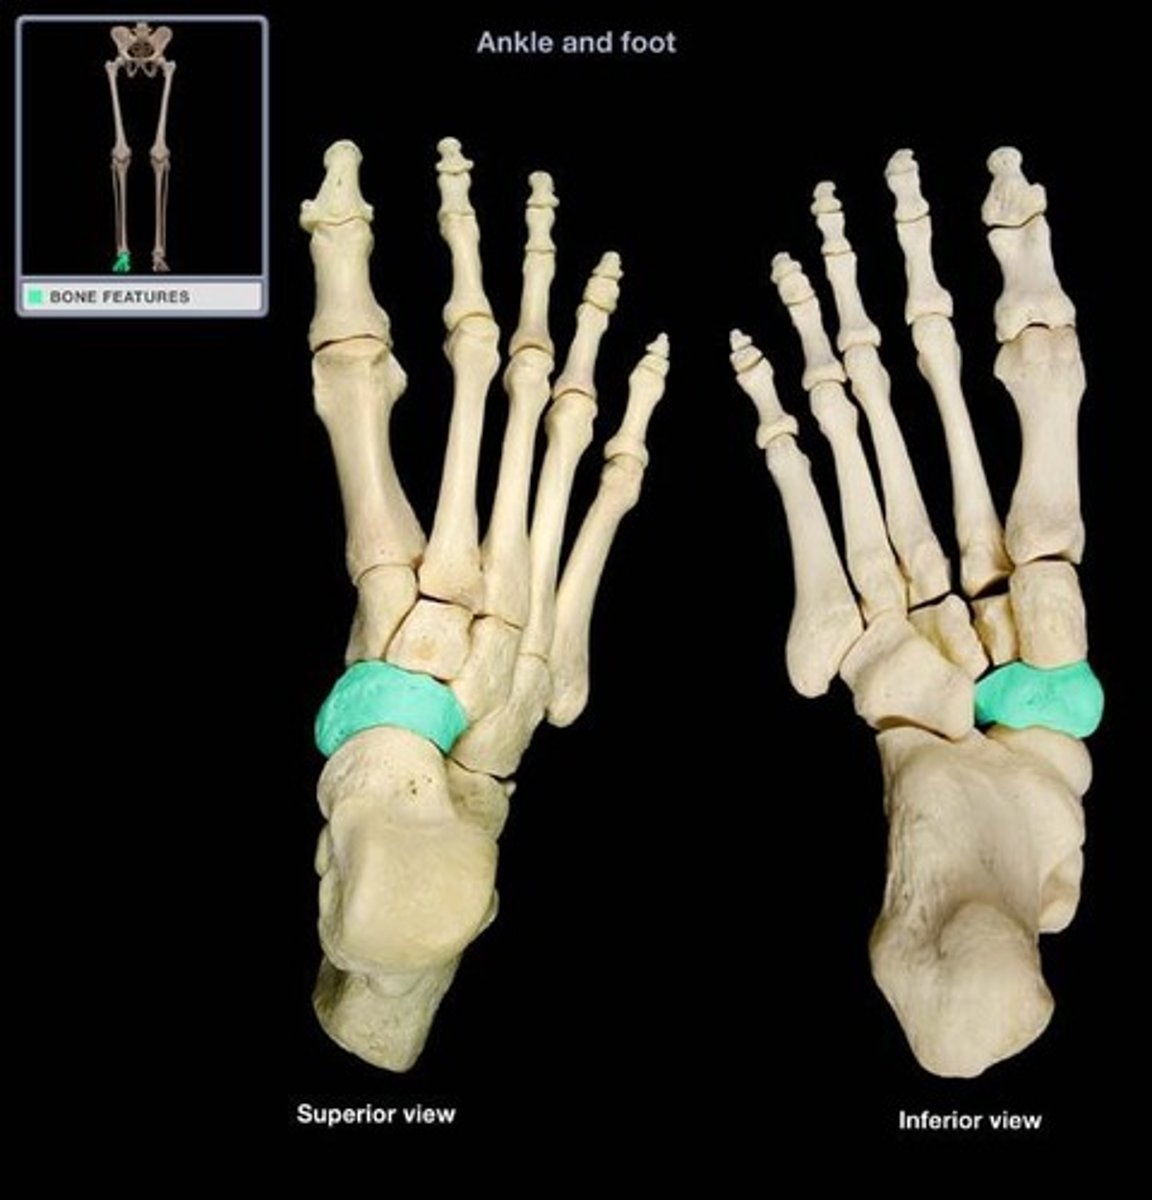

Navicular

What is the term of the bones highlighted in green?

Medial Cuneiform

Intermediate Cuneiform

Lateral Cuneiform

Cuboid

Metatarsals